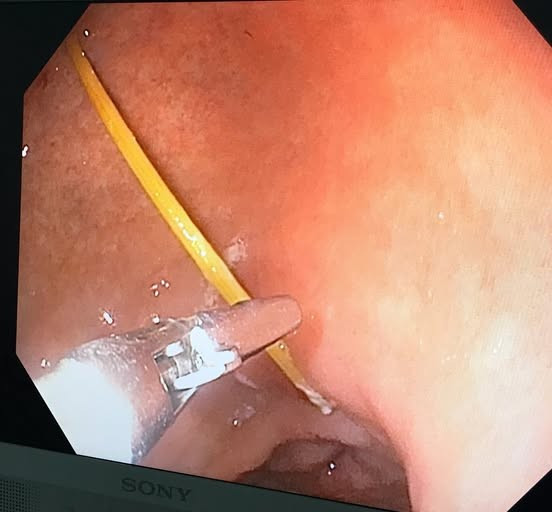

Mới đây các bác sĩ Bệnh viện Hữu Nghị đã tiến hành nội soi và gắp dị vật là chiếc tăm dài gần 7cm trong dạ dày một người bệnh trú tại Hà nội.

Các bác sĩ đã tiến hành nội soi gắp 1 chiếc tăm nhọn dài gần 7cm 1 đầu găm vào thành dạ dày và đã tạo thành ổ loét tại dạ dày người bệnh...

Tăm tre đâm thủng dạ dày tạo ổ áp xe - Ảnh BVCC